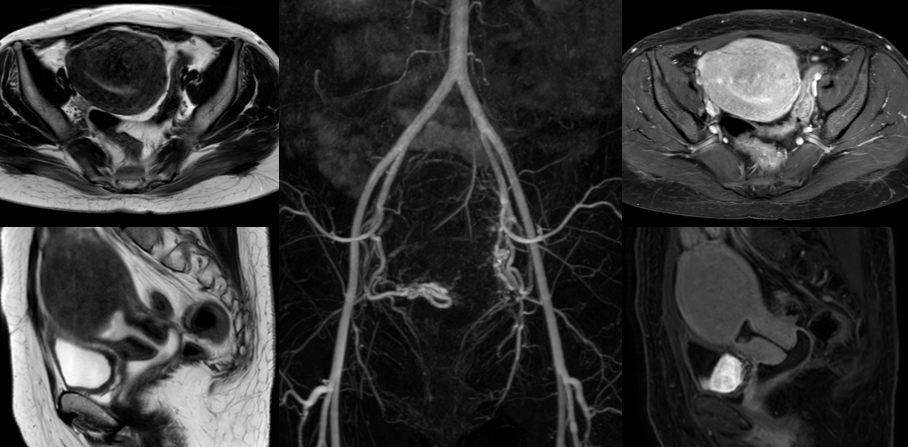

39岁的曾女士,一天上洗手间的次数竟是普通人的三倍之多,来例假时痛经不光肚子疼,连腰骶部都坠胀得难受,经常在经期疼得直不起腰,严重影响了她的工作生活。而且月经量也比以前明显增多,体力降低,易疲劳。以往家住5楼的她一口气可以爬上去,而如今,5层楼她中途需要歇个两三回。同时,曾女士还发现自己的小肚子日益增大,小便也越来越憋不住了,出门在外一有尿感就得赶快找厕所。这样的尿频、尿急情况持续了一年之久。刚开始她只觉得自己是因为上了年纪,身体素质下降而导致的痛经和尿频,直到后来月经出现淋漓不净,这才考虑到是妇科疾病,到当地医院就诊,诊断是子宫腺肌病,医生建议,如果曾女士不打算生娃就把子宫切除了。后来曾女士开始在网上搜索各种资料,她看到一篇公众号得知子宫腺肌症导致的痛经、尿频、尿急可以通过”介入微创保宫治疗“好转。曾女士遂在“广东省第二人民医院公众号”上挂号预约韦文姜副主任医师的号后来到广东省第二人民医院介入血管科门诊就诊,门诊磁共振MRA检查显示:“子宫明显增大,大小约为108mm*92mm*63mm”(如下图),“子宫腺肌症”也就是导致曾女士经期痛不欲生、尿频、夜尿增多的元凶。